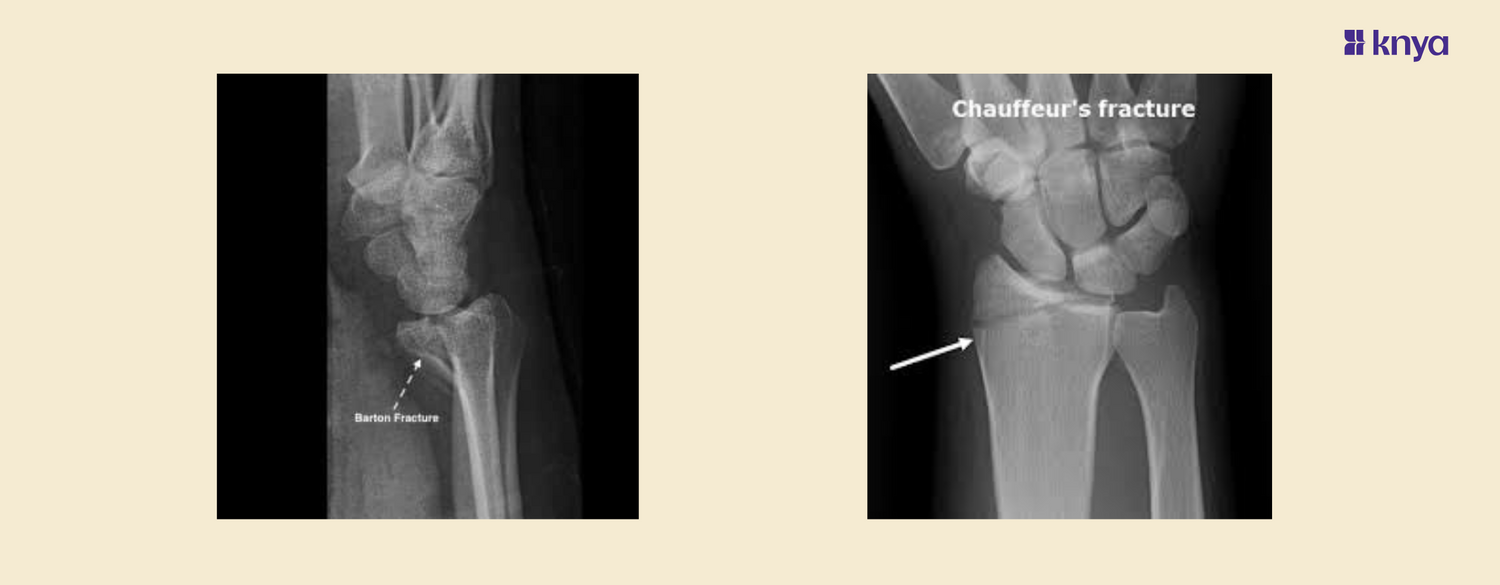

What is Chauffeur's Fracture?

A Chauffeurโs fracture, also known as a Hutchinson fracture, is an intra-articular fracture of the radial styloid process. It was originally termed "chauffeurโs fracture" because early 20th-century chauffeurs often sustained this injury when hand-cranking cars backfired.This type of fracture is commonly caused by a direct blow to the wrist or a fall onto an outstretched hand with the wrist in radial deviation. It can also result from high-energy trauma such as motor vehicle accidents.

Diagnosis

Diagnosis is typically made through physical examination and confirmed with imaging studies.ย

- X-rays are essential to visualize the fracture.

- ย MRI or CT scans can be used to assess associated soft tissue injuries.